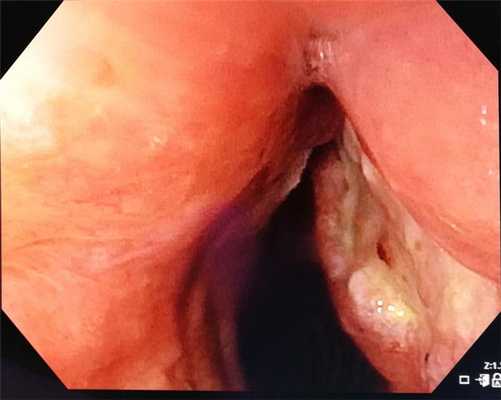

варикозное расширение вен прямой кишки при циррозе